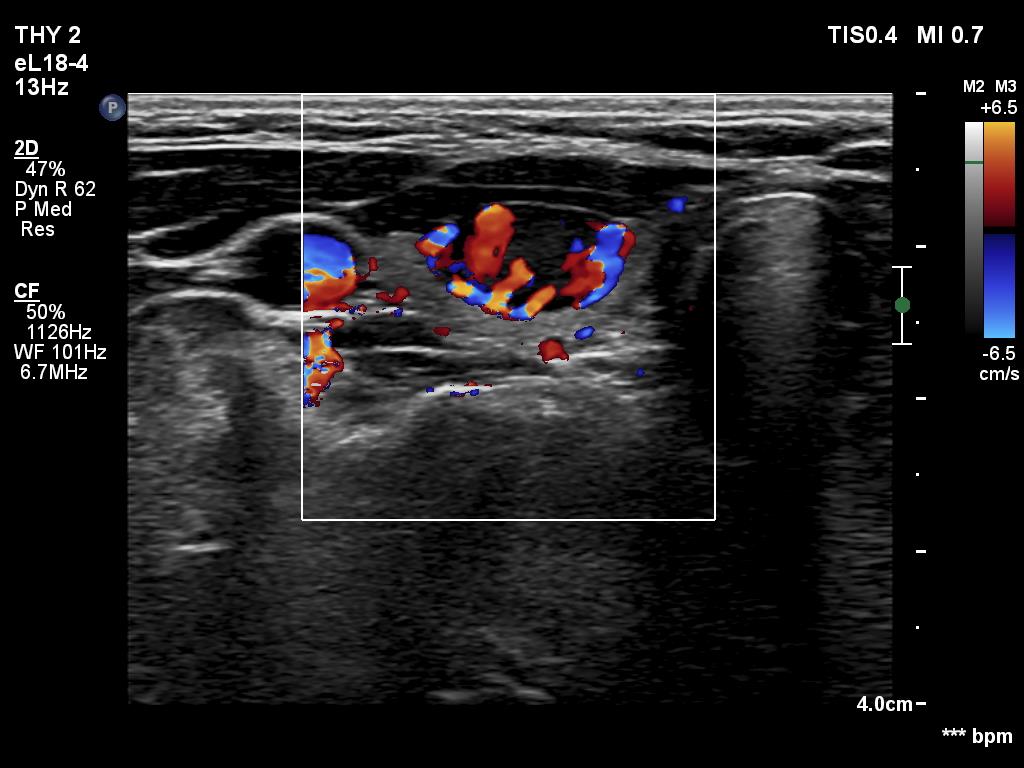

Ultrasonography. The thyroid was echonormal. There was a moderately hypoechoic nodule in the ventral part of the right lobe. This lesion has regular, sharp margins and presented signs of a possible extrathyroidal spread. The intranodular vascularity was increased. The left lobe had a tiny, minimally hypoechoic lesion. The largest diameter was 7 mm. The lesion had both echogenic lines and granules, a pattern corresponding either to connective tissue or back wall figure. The lesion had neither halo nor perinodular blood flow.

The nodule in the right lobe is remarkable because of the hypoechogenicity, the increased vascularity and because it shows sing of a possible extrathyroidal spread.

The third was the handling of the cytology. This was not the failure of the colleagues but the failure of our current practice. If we follow the suggestions, we cannot take clinical or ultrasound data into account when giving a cytological diagnosis. It is very strange because in the histopathological diagnosis, these data are taken into account. Moreover, while in histopathology, the consideration of these data only rarely influences the final diagnosis, in cytology, this consideration would have a huge impact. Regarding this case, a nodule which does not show any ultrasound signs of a capsule, is unlikely a follicular tumor; this lesion did not have either a halo sign or perinodular blood flow.